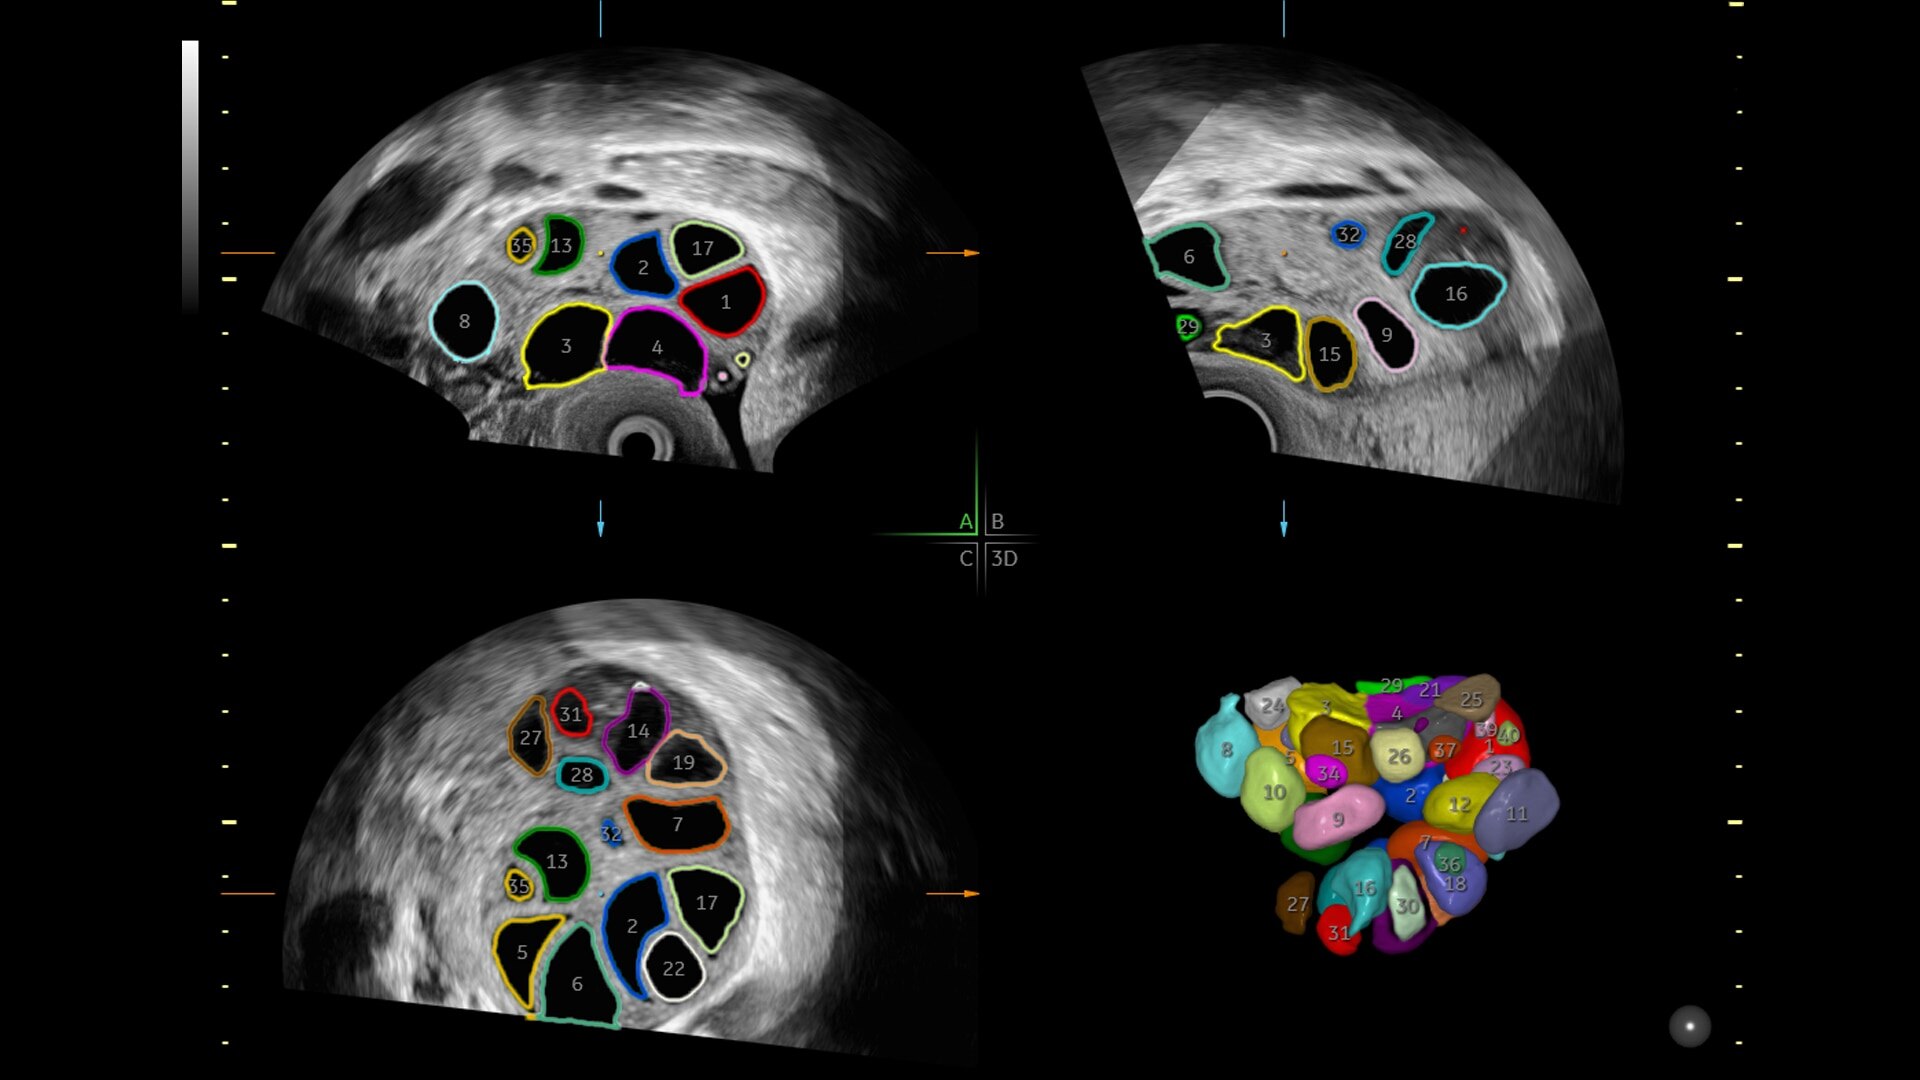

SonoCNS reduces brain assessment exam time by 81%

Reduce keystrokes by 83% with 3D Spine Trace